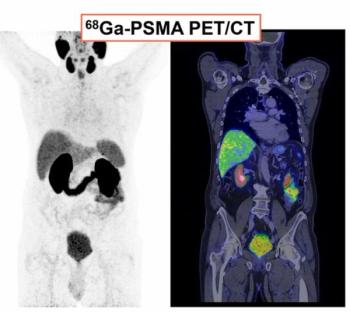

PSMA PET/CT Facilitates Better Long-Term Survival Rates After Salvage Radiotherapy for Recurrent PCa

Patient with biochemical recurrence of prostate cancer who had PSMA PET/CT prior to salvage radiotherapy had better survival rates at one, two and five years, according to newly published research.